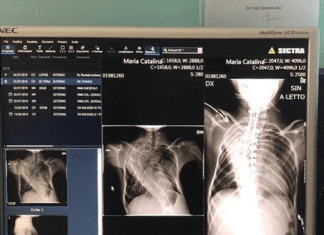

(Radiografia coloanei Mariei-Cătălina, înainte şi după operaţie)